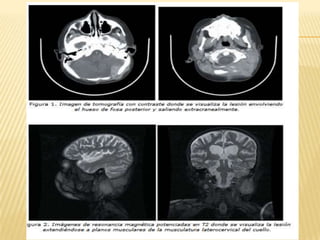

   La imagen de resonancia magnética permite la localización anatómica de la

lesión, las características tisulares del tumor y la vascularidad. Este método

con gadolinio es también sensible para evaluar la metástasis subaracnoidea

de la médula espinal. Debido a que en algunas ocasiones el meduloblastoma se

disemina fuera del sistema nervioso central, especialmente al hueso, puede que

sea útil una exploración ósea con gamagrafía ósea, así como una biopsia de

médula ósea en los pacientes sintomáticos o con niveles anormales de

hemoglobina.